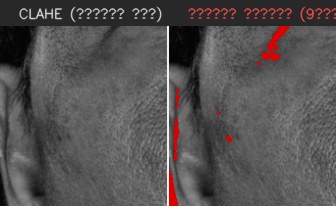

이마

유효 주름 수 4개 · 주 방향 가로

상위 깊이(평균 상위3) 0.320 mm

| # | 길이(mm) | 깊이(mm) | 유효 판정 근거 |

|---|---|---|---|

| 1 | 8.63 | 0.110 | 대표 깊이 0.110 mm가 이 부위 최소 깊이 0.100 mm 이상이고, 유효 길이 8.63 mm가 최소 길이 5.00 mm 이상이어서 노이즈·미세선과 구분되어 유효 주름으로 집계되었습니다. |

| 2 | 10.47 | 0.161 | 대표 깊이 0.161 mm가 이 부위 최소 깊이 0.100 mm 이상이고, 유효 길이 10.47 mm가 최소 길이 5.00 mm 이상이어서 노이즈·미세선과 구분되어 유효 주름으로 집계되었습니다. |

| 3 | 5.76 | 0.322 | 대표 깊이 0.322 mm가 이 부위 최소 깊이 0.100 mm 이상이고, 유효 길이 5.76 mm가 최소 길이 5.00 mm 이상이어서 노이즈·미세선과 구분되어 유효 주름으로 집계되었습니다. |

| 4 | 14.61 | 0.477 | 대표 깊이 0.477 mm가 이 부위 최소 깊이 0.100 mm 이상이고, 유효 길이 14.61 mm가 최소 길이 5.00 mm 이상이어서 노이즈·미세선과 구분되어 유효 주름으로 집계되었습니다. |